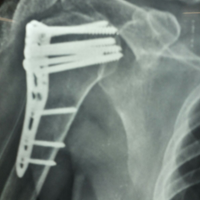

Post-op